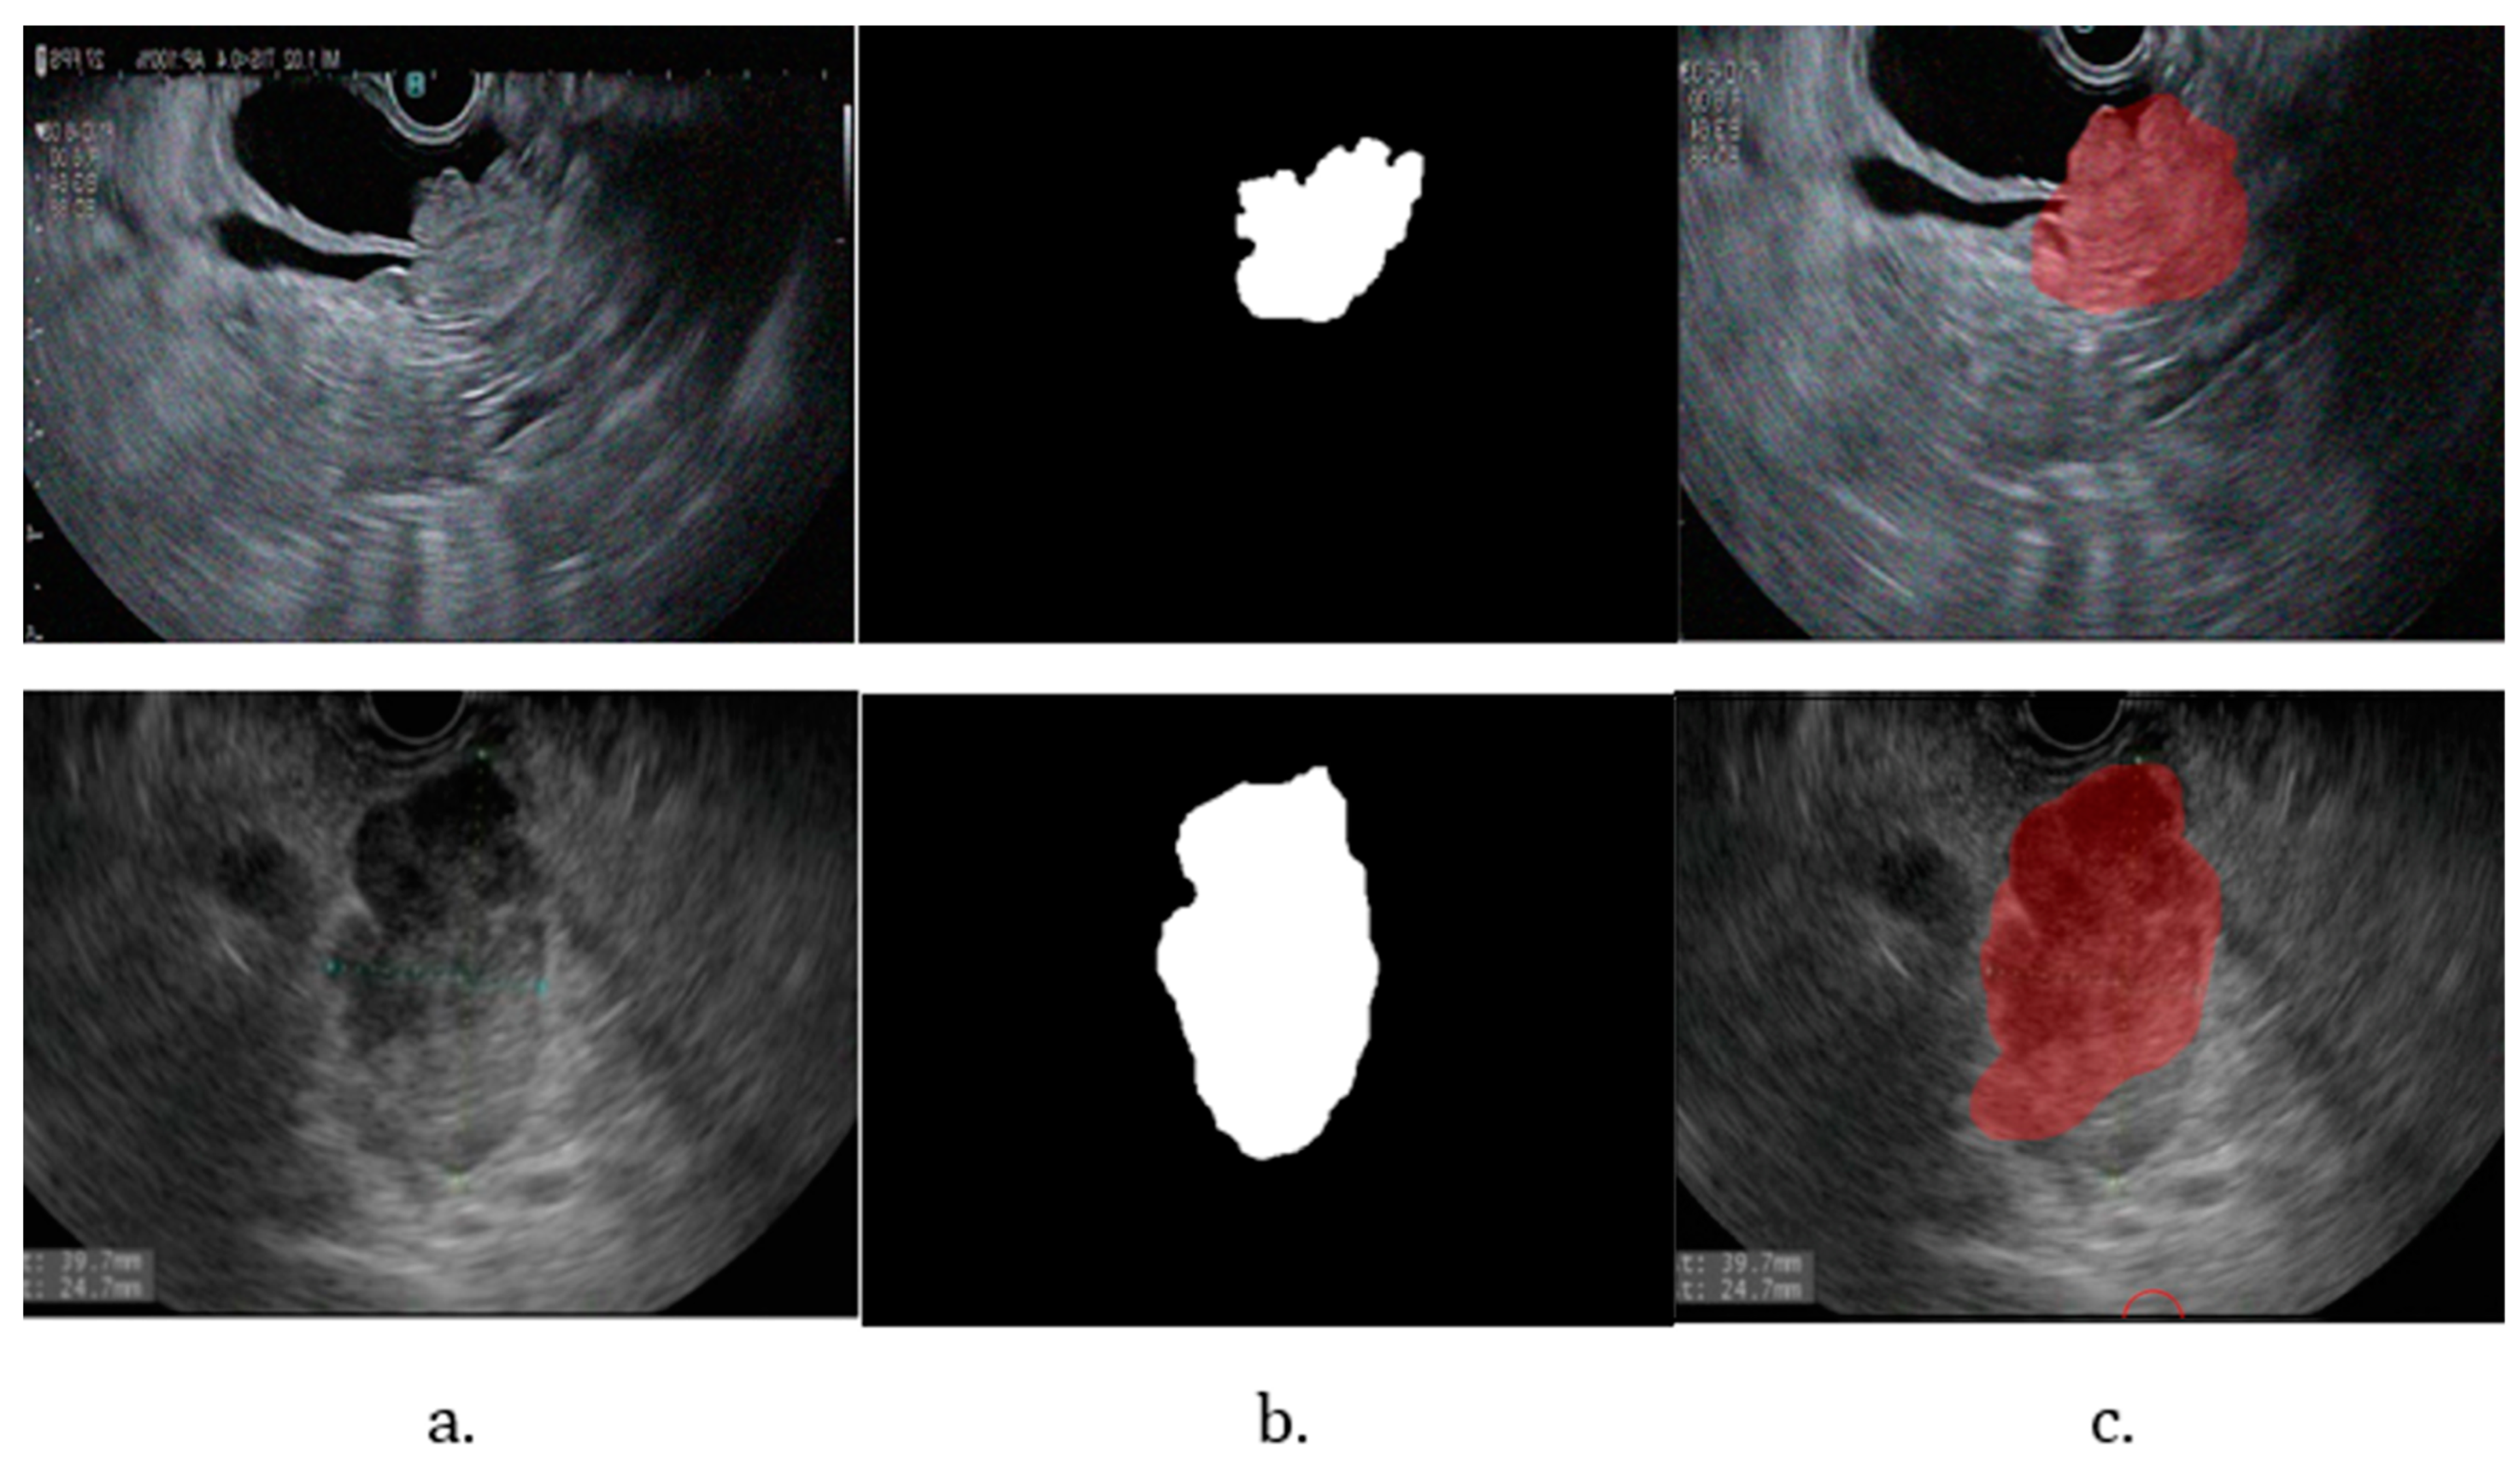

Given the limited size of the dataset, image augmentation was necessary to increase its diversity and ensure the model could handle the variability of real-life images. Augmentation techniques applied included random rotations between −30 and +30 degrees, horizontal mirroring, random translations on the X and Y axes up to +/− 10 pixels, random scaling between 0.9 and 1.1 times the original size, and adding Gaussian noise with mean 0 and variance 0.01. Each original image was augmented to create approximately eight additional copies, each with one of these techniques applied randomly. This process resulted in 848 images containing tumors and 400 images with a healthy pancreas. To ensure compatibility with the model’s input requirements, all images and corresponding labels were resized to 256 × 256 pixels. This uniform resizing enabled the training of the convolutional neural network (CNN), prevented errors due to varying image sizes, and ensured consistency across the dataset. Training the CNN for detection and segmentation required both the original images and binary masks corresponding to the labeled organs. These masks, created from the labeled images, denoted the tumor, pancreas, and bile duct regions. An example of an image and its corresponding mask is presented in Figure 1.

Figure 1. (a) EUS aspect of a dCCA; (b) binary mask for tumor.